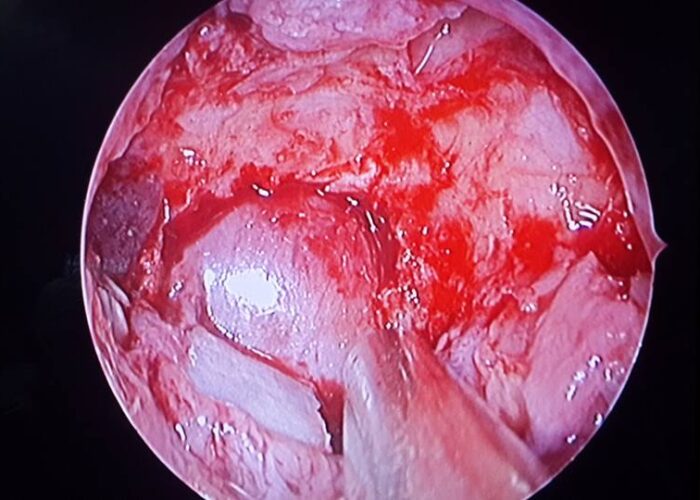

3 Endoscopic Pituitary Cases in Manik Hospital